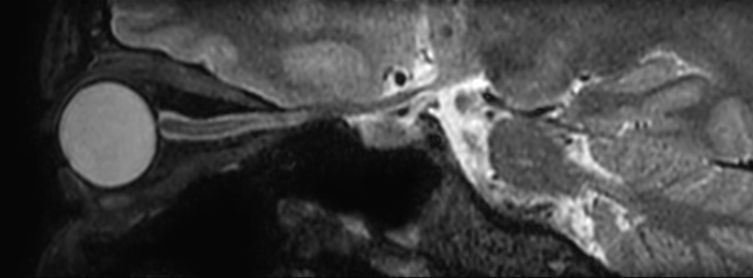

Sagittal 3D VIEW - T1w TSE

Pre-Gado